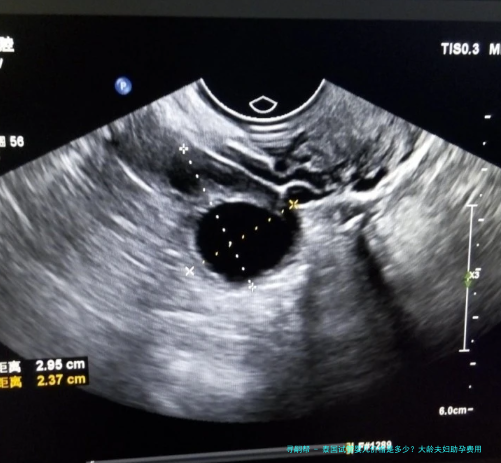

1.术前检查费用:平常在5000-8000元人民币左右。这囊括男女两边的身体检查,如血常规、激素水平、传染病筛查、B超、精液解析等,旨在评估体质状况,排除不利因素。